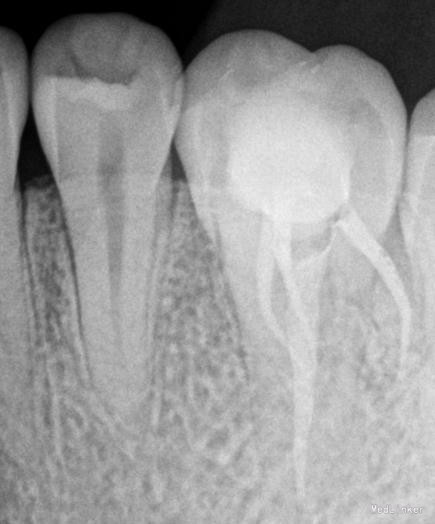

诊断:#26牙髓炎 治疗计划:#26根管治疗,后期纤维桩加固嵌体保护冠修复。局部麻醉下开髓,根管预备,消毒。(近中发现mb2)

根管疏通,弯曲根管预备时可选用先锋锉或不锈钢k锉进行预弯,注意预备时用edta充满髓腔和根管,初尖锉可。